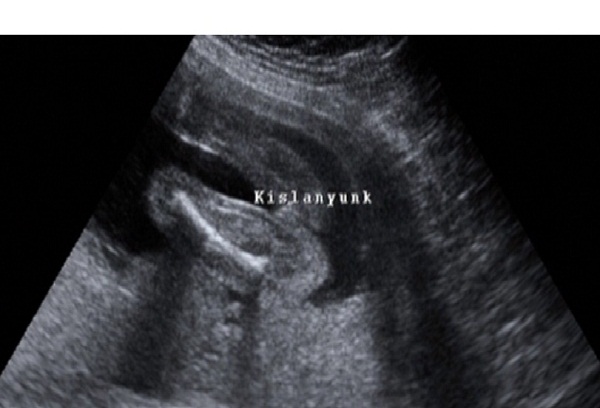

Gratulálok a kislányhoz!!

Akkor nem gazdagítjátok tovább a 4D bizniszt?